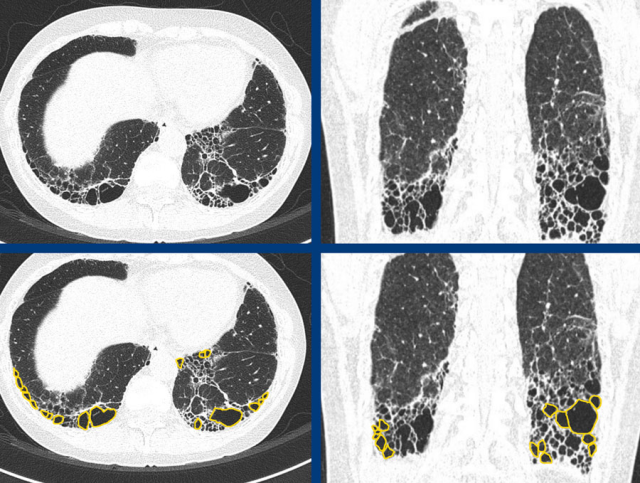

In A there is honeycombing combined with basal and subpleural dominant fibrosis indicating a definite UIP pattern.

In B there is a probable UIP pattern without honeycombing.